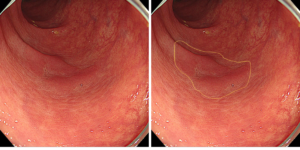

中央の部分に発赤調の平坦に隆起している病変が見えてきましたでしょうか。

NBI観察、インジゴカルミンを散布することによって病変の境界がしっかりと認識できますね。

分かりましたね?

見つけましたね?

見つけられましたか?・・・さすがです!!